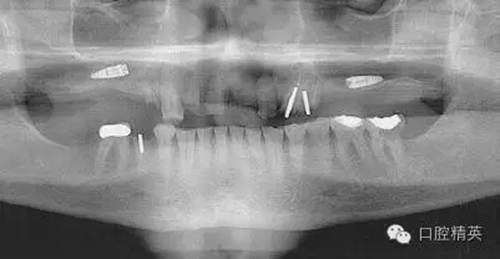

圖2a:術后曲面斷層片顯示兩顆種植體分別異位于左右側上頜竇中

圖7a:6,7號牙種植體(3*15mm)折斷前,從物理學理論上講,種植體骨整合后,基臺螺絲和種植體相連接的支點處是受力時種植體最薄弱的位置。(a)可見6號牙種植體的折斷面,和7號牙種植體上的折裂線(b)

圖7b:6,7號牙種植體折斷后。

圖7c,d:6,7號牙的回顧性模型分析顯示為了獲得滿意的美學效果牙冠不得不做的很長,從而形成較深的咬合關系。同時可見對

頜牙磨耗嚴重,廣泛。